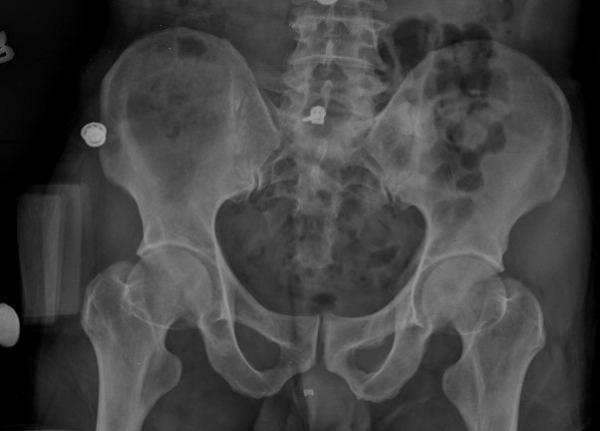

ŽÃËÀÚ¸¦ ¾ûµ¢ÀÌ °üÀý ¿ÜÃø Á¾´Ü¸é°Ë»ç ½Ã ÀüÇÏÀ屨(AIIS)¿¡¼­ ¼®È¸È­¼º À½¿µÀÌ °üÂûµÊ(»çÁø 2, 3).

ÃÊÁø ½Ã ½ÃÇàÇÑ ¹æ»ç¼± ÃÔ¿µ»ó ÀüÇÏÀ屨 ºÎÀ§¿¡¼­ ¼®È¸È­ À½¿µÀÌ °üÂûµÇ°í, 3ÁÖ ÈÄ ½ÃÇàÇÑ ÃÔ¿µ¿¡¼­

¼®È¸È­ À½¿µ ¼Ò½ÇÀÌ È®ÀεÊ.